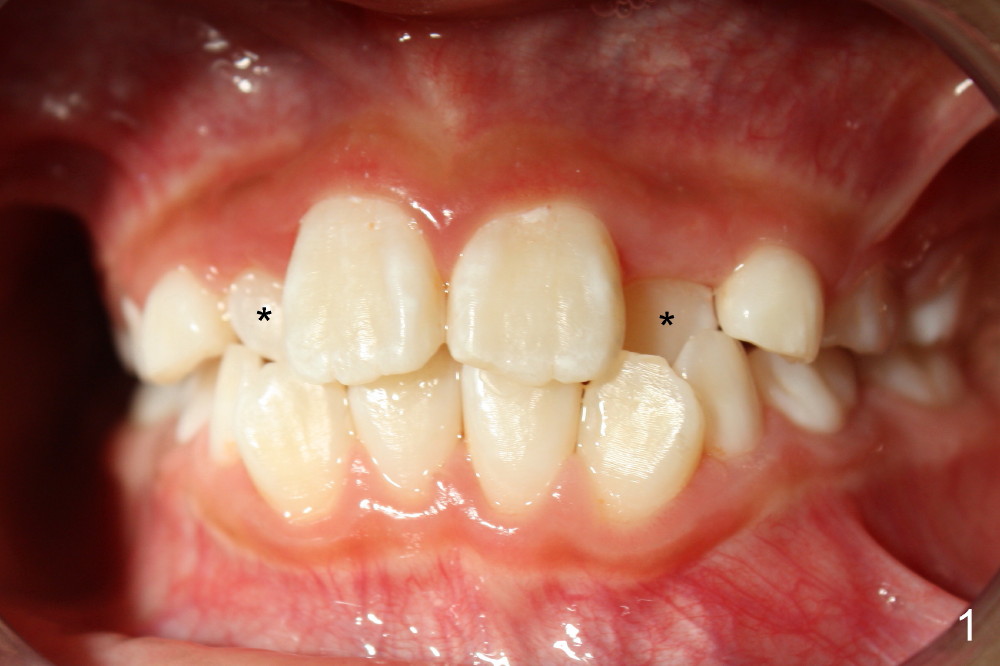

Six months earlier, the tooth #7 is erupting lingually. Now at the age of 8, both of the upper lateral incisors are in cross bite (Fig.1*). It appears that the cross bite is due to jaw deficiency in anteroposterior direction. In fact, these two laterals are blocked because there is not enough space transversely (Fig.2). Posterior occlusion is Class I bilaterally (Fig.3,4). The lower incisors are also crowded. Therefore early comprehensive orthodontic treatment has the most important component: palatal expander. In our previous case, unilateral cross bite resolves rapidly after the palate is expanded.